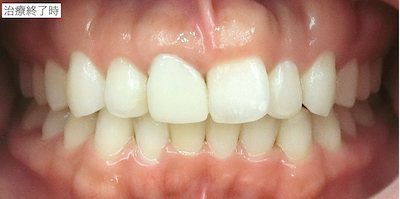

再度ファイバーポストで支台築造後、仮歯作成し、光学印象ののちにセラミッククラウンを装着しました。

治療前後の比較です。

通常のホワイトニングやセラミック冠の装着に比べて治療期間や費用はかかりましたが、他院さんで既に受けてこられた矯正治療期間や矯正治療費用に比べるととても少なかったため、治療結果も含めて、患者さんはとても喜んで下さいました。

治療名:エクストルージョン、CEREC審美治療

総治療期間:約3ヶ月(ホームホワイトニング〜エクストルージョン〜セラミック装着)

費用:CEREC治療(1本分)約15万円 ファイバーポストによる支台築造費用、エクストルージョン、ホームホワイトニングを含む